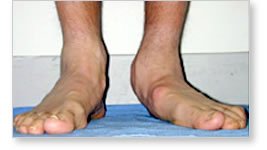

These pictures are of a 16-year-old boy with a tarsal coalition

of one foot. Note how flat the foot is. |